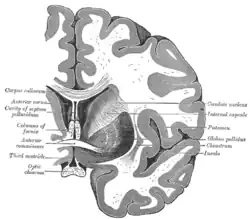

Commissura anterior, auch Commissura rostralis (von lateinisch rostrum ‚Schnabel‘), bezeichnet eine der Kommissuren des Endhirns, die als Querbahn unter anderem die beiden Temporallappen miteinander verbindet. Des Weiteren kreuzen hier Anteile der Riechbahn die Seite. Die Commissura anterior befindet sich rostral des dritten Ventrikels über der Lamina terminalis.

Die anderen Querbahnen des Telencephalons sind das Corpus callosum und die Commissura fornicis. Die Commissura habenularis und die Commissura posterior (auch Commissura epithalamica genannt) sind dagegen dem Epithalamus und damit dem Zwischenhirn zugeordnet.

Eine gedachte Verbindungslinie zwischen der Commissura anterior und der Commissura posterior findet in der Neuroradiologie wie auch in der Neurochirurgie Verwendung als Orientierungshilfe (englische Abkürzung „AC-PC line“[1]).